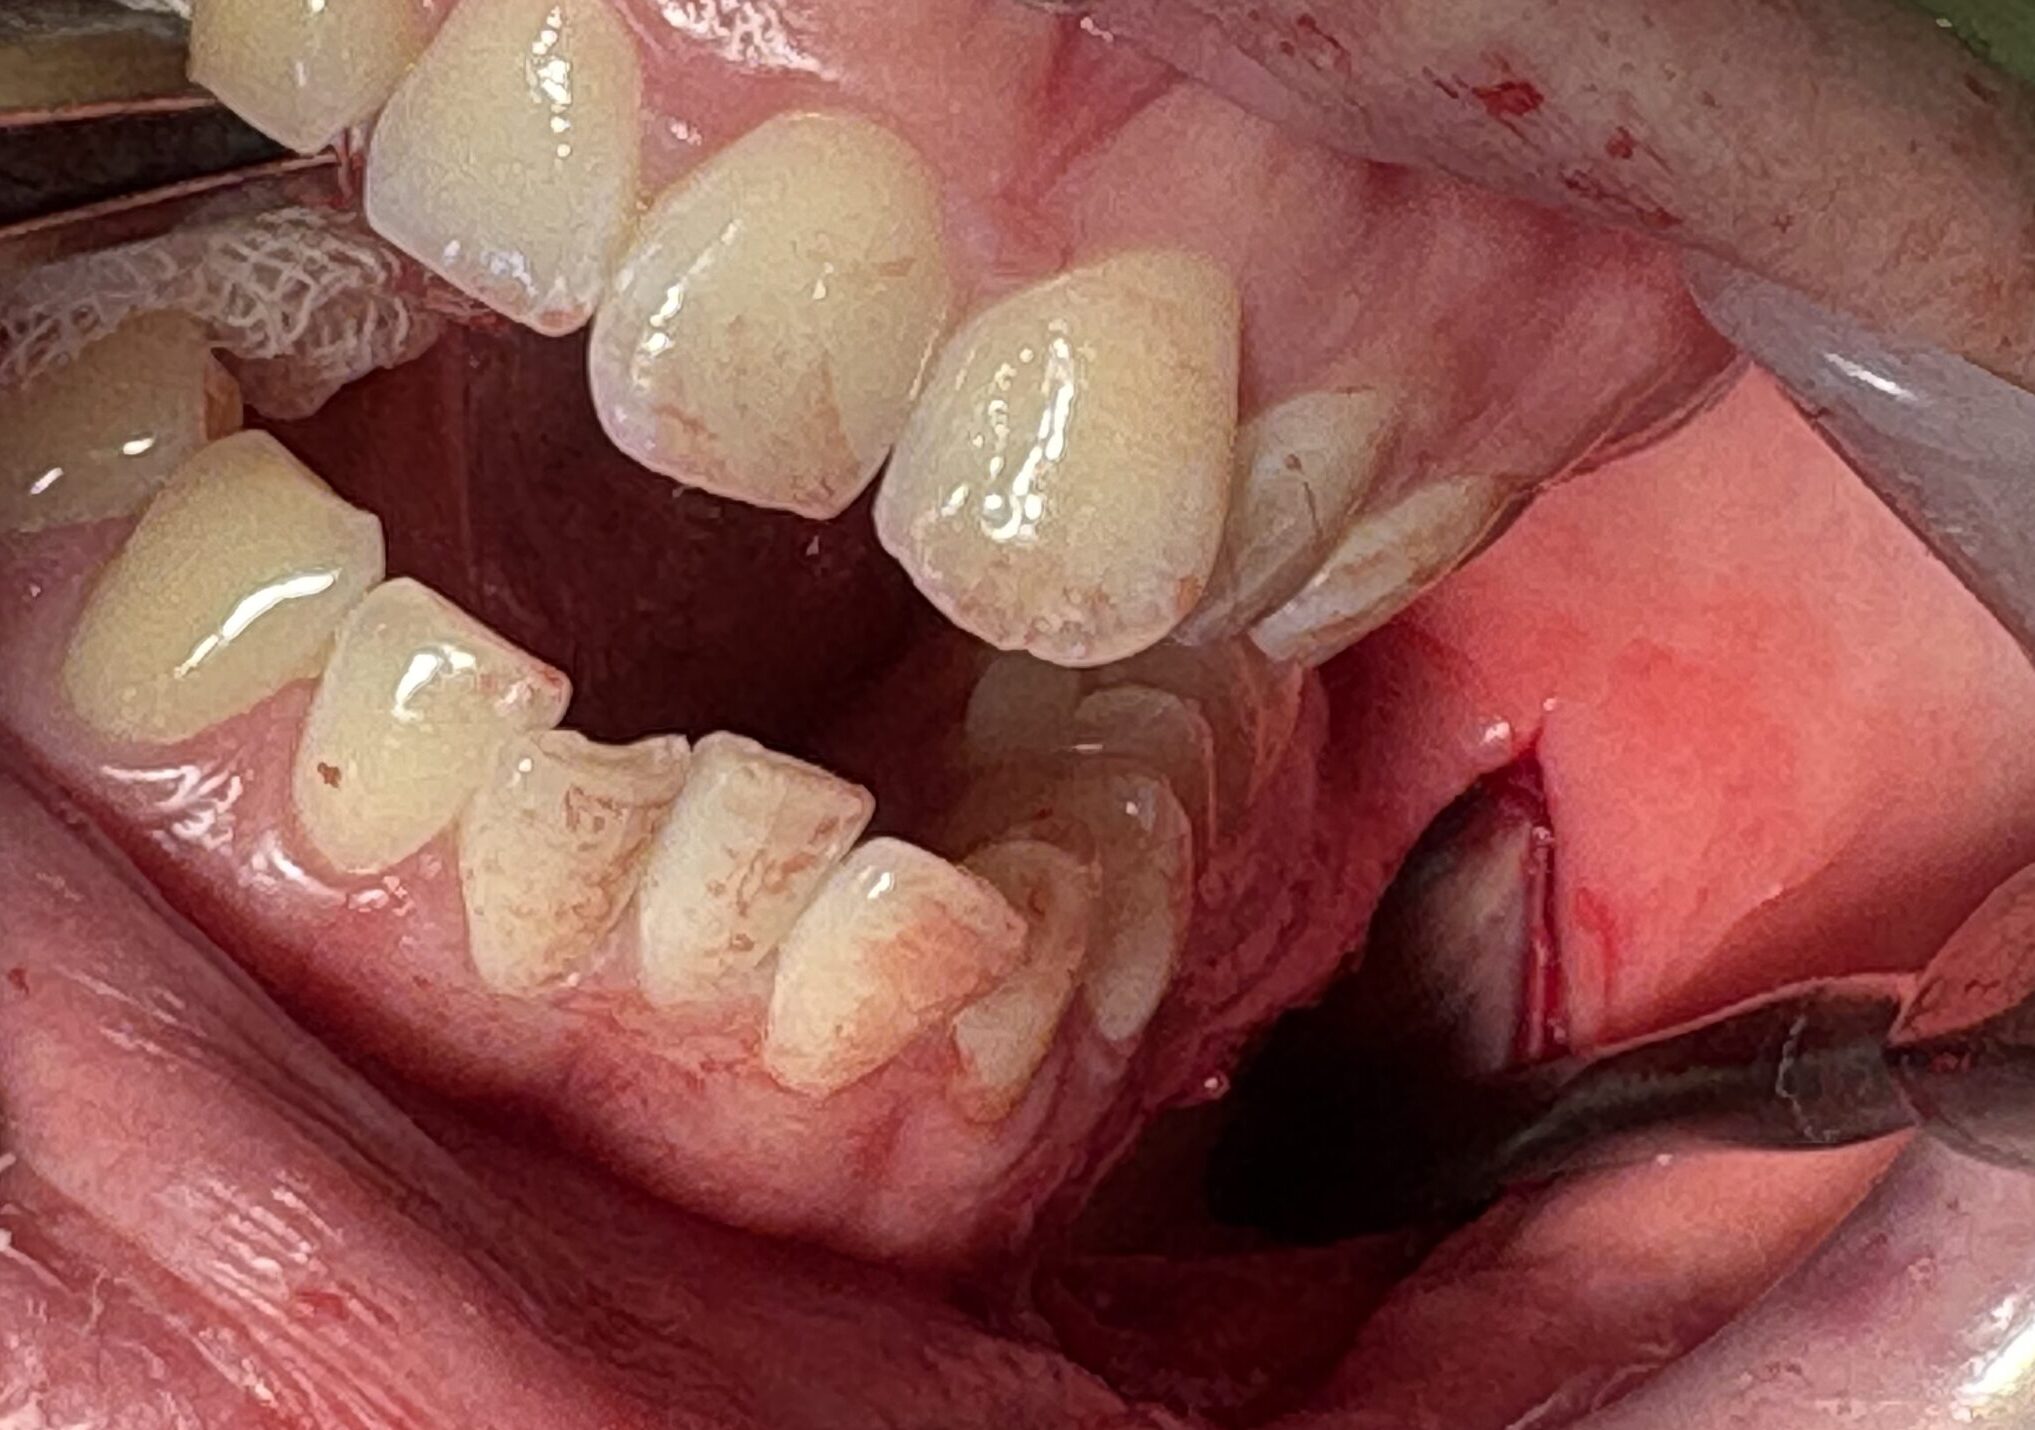

切除した骨です。

反対側も同様の骨切りを行い、左右差が出ないようにします。

画像の左側(患者様の右側)のコツ切りラインです。オトガイ神経はしっかりとほぐしてあるので、よく伸展されていて、切れることはなく、手術後の神経障害も出にくいメリットがあります。

左右の切除骨と真ん中の短縮部分を中抜きして切除した骨です。